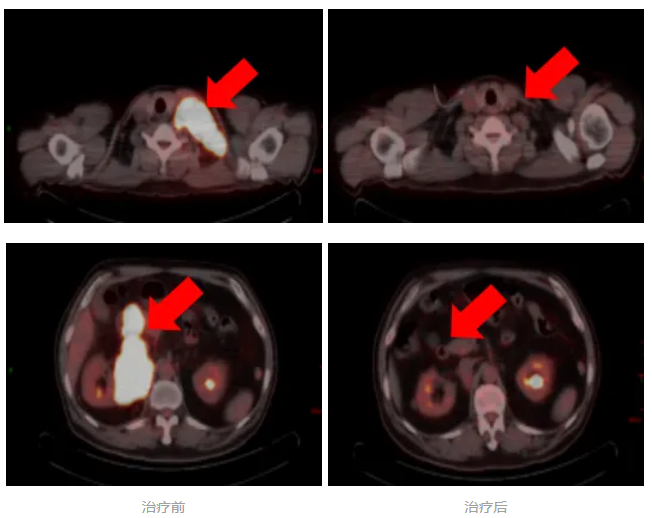

日前,一例高危、双表达型弥漫大B细胞淋巴瘤患者,在我院淋巴瘤及头颈肿瘤内科接受个体化精准治疗后,病情得到有效控制,疗效评价达到完全缓解(CR)。

患者因左颈部肿物就诊我院,经穿刺活检初步诊断为弥漫大B细胞淋巴瘤。为全面评估病情,医疗团队进一步完善检查,最终明确为高危型弥漫大B细胞淋巴瘤,已广泛累及淋巴结、肠管及胰腺,治疗难度较大。

面对这一情况,淋巴瘤及头颈肿瘤内科林剑扬主任医师团队为患者制定了标准靶向化疗(RCHOP方案)联合中枢预防的个体化治疗方案。

经4周期治疗后,评估为部分缓解(PR)。为改善患者预后,MDT团队再次讨论并与患者沟通后,在后续治疗中加用组蛋白去乙酰化酶抑制剂。完成系统治疗后复查显示,患者最终达到完全缓解。

林剑扬主任医师介绍,该患者治疗前期疗效评估为部分缓解后,团队及时将方案调整为RCHOP。这一决策基于前沿循证医学依据,通过表观遗传调控与免疫化疗的协同,旨在克服肿瘤耐药,属于个体化治疗的精准升级。本例的成功救治,充分体现了我院淋巴瘤诊疗中心紧跟国际前沿、践行精准医疗与全程管理的综合能力。